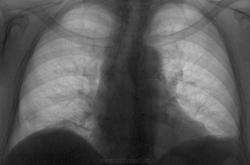

Пол пациента: Женский пол Тип патологии: Сосудистое заболевание Область исследования: Грудная клетка и верхние дыхательные пути Методы исследования: Rg Ровно 2 года между этими флюшками. Прицепился к "кругляшку" справа над диафрагмой. А как Вы думаете, стоило ли? https://radiomed.ru/sites/default/files/styles/case_slider_image/public/user/3055/1938_g.r.06.11.2013g.jpg?itok=rDXzk1M_ ID:33211 Ср, 13/11/2013 - 12:25 #1 Helios Не на сайте Был на сайте: 7 месяцев 2 недели назад Зарегистрирован: 06.08.2010 - 15:16 Публикации: 4417 Стоило.И купол подтянулся, кажется.Или не довдохнул? Ср, 13/11/2013 - 13:38 #2 stovbav Не на сайте Был на сайте: 2 года 2 месяцев назад Зарегистрирован: 20.12.2009 - 17:28 Публикации: 7066 Стоило. Периферический на первое место. Болезни ног: виды, симптомы, причины, профилактика и лечение Ср, 13/11/2013 - 19:16 #3 Сергей Кузьминов Не на сайте Был на сайте: 1 год 1 неделя назад Зарегистрирован: 06.10.2012 - 15:51 Публикации: 11813 Стоило цепляться.Как будете дообследовать? Ср, 13/11/2013 - 19:56 #4 Игорь Иванович Не на сайте Был на сайте: 3 года 9 месяцев назад Зарегистрирован: 23.01.2010 - 14:56 Публикации: 3695 Сергей Кузьминов wrote: Стоило цепляться.Как будете дообследовать? Приложения: Ср, 13/11/2013 - 20:14 #5 Дмитрий Волегов Не на сайте Был на сайте: 3 года 6 месяцев назад Зарегистрирован: 22.05.2013 - 00:32 Публикации: 1148 Наверное можно пошутить?, а то грустно. Противоспалительная терапия - это хорошо. Поможет убрать любые воспалительные изменения в любом месте. Диагноз - будет зависить от того, что именно и в каком месте уберется. С Уважением, Дмитрий. Ср, 13/11/2013 - 21:44 #6 Сергей Кузьминов Не на сайте Был на сайте: 1 год 1 неделя назад Зарегистрирован: 06.10.2012 - 15:51 Публикации: 11813 Ну куда же флюорографом супротив томографа. Чт, 14/11/2013 - 08:25 #7 Игорь Иванович Не на сайте Был на сайте: 3 года 9 месяцев назад Зарегистрирован: 23.01.2010 - 14:56 Публикации: 3695 Сергей Кузьминов wrote: Ну куда же флюорографом супротив томографа. Меня больше всего умиляет фраза - СКТ контроль после проведенного лечения. Пт, 15/11/2013 - 02:23 #8 Makcimalist Не на сайте Был на сайте: 11 лет 8 месяцев назад Зарегистрирован: 08.05.2010 - 14:28 Публикации: 1994 Игорь Иванович wrote: Сергей Кузьминов wrote: Ну куда же флюорографом супротив томографа. Меня больше всего умиляет фраза - СКТ контроль после проведенного лечения. Это как для нас контрольный снимок - ничего удивительного. Любят свою работу, ребята.) Жаль, лучевая нагрузка не волнует.( -------------- "Просто, по видимости, не видеть логики в очевидных вещах - это тоже одно из свойств некоторых умов, наряду с грустными думами о свойствах ума других." © Vega 08/10/2011

Стоило.И купол подтянулся, кажется.Или не довдохнул?

Стоило. Периферический на первое место.

Стоило цепляться.Как будете дообследовать?

Ну куда же флюорографом супротив томографа.

Меня больше всего умиляет фраза - СКТ контроль после проведенного лечения.